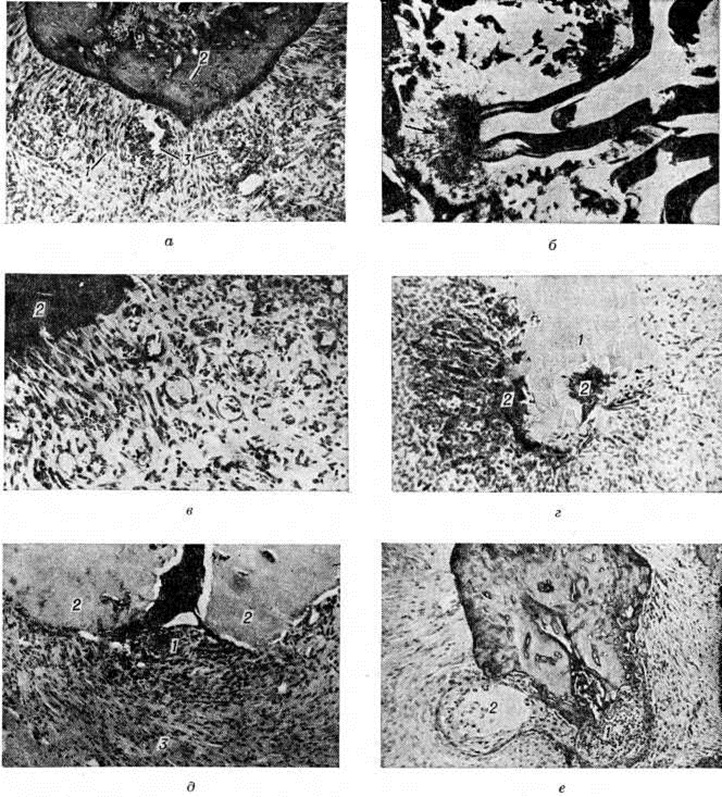

Как правило, периодонт в отдельных участках пропитан серозным экссудатом с небольшой примесью лейкоцитов и круглоклеточных элементов. Лишь местами обнаруживают преимущественно периваскулярные компактные скопления лейкоцитов (рисунок 1, а). Прогрессирование серозного Периодонтит обусловливает его переход в гнойный Периодонтит, при котором макроскопически в утолщённом и полнокровном периодонте видны желтоватые очажки — гнойнички. В случае гнойного расплавления периодонта на поверхности корня зуба сохраняются лишь отдельные его фрагменты, остальная часть корня обнажена, покрыта гноем. Нередко в области больного зуба наблюдают воспалительную гиперемию и отёк надкостницы альвеолярного отростка и слизистой оболочки десны. Микроскопически в толще периодонта, окружающего верхушку корня зуба, на фоне резкой гиперемии видны очаговые и диффузные лейкоцитарные инфильтраты. Как правило, наблюдаются множественные микроабсцессы, в результате слияния которых в около-верхушечной области образуются более крупные абсцессы (рисунок 1, б). Обычно вокруг абсцесса формируется зона перифокального серозного воспаления, которая в виде пояса отграничивает абсцесс от окружающих тканей. В других случаях отмечается распространение серозно-гнойного и гнойного процесса на прилежащие участки костной ткани. При этом патологический процесс сопровождается незначительной либо умеренной резорбцией костной стенки зубной альвеолы, а также цемента корня зуба. Острый Периодонтит в некоторых случаях переходит в хронический. В зависимости от характера тканевой реакции различают гранулирующий, гранулематозный, фиброзный и обострившийся хронический Периодонтит При гранулирующем Периодонтит макроскопически на отдельных участках верхушки корня удалённого зуба видны обрывки сочной темно-красного цвета грануляционной ткани. Поверхность корня неровная, шероховатая, с единичными либо множественными узурами. Микроскопически в окружности верхушки корня зуба обнаруживается не имеющее чётких границ разрастание грануляционной ткани на различных стадиях созревания (рисунок 1, в). В области разрастания грануляционной ткани наблюдается интенсивная резорбция твёрдых тканей корня зуба (цемента и дентина), а также костной стенки зубной альвеолы (рисунок 1, г). Грануляции замещают собой костную ткань и в отдельных случаях, резорбировав компактное вещество кости челюсти и разрушая надкостницу, прорастают в около-челюстные мягкие ткани. Наряду с рассасыванием твёрдых тканей зуба и кости но периферии воспалительного очага наблюдается и их новообразование. В прилежащих к воспалительному очагу участках костной ткани повсеместно выявляют гиперемию, отёк, очаговые и диффузные лимфогистиоцитарные инфильтраты. Происходит замещение костного мозга соединительной тканью. Гранулематозный периодонтит по морфологический признакам делят на простую зубную гранулему, сложную зубную гранулему и кистогранулему. Макроскопически зубные гранулемы имеют вид шаровидного или овального образования, окружённого плотной фиброзной оболочкой, обычно с гладкой поверхностью, припаянного к верхушке корня зуба, благодаря чему гранулема нередко извлекается вместе с удалённым корнем. Окраска зубных гранулем различна — от светло-жёлтой до темно-красной. Простая зубная гранулема микроскопически характеризуется образованием фокуса созревающей грануляционной ткани, отграниченного по периферии фиброзной капсулой различной толщины (рисунок 1,д). Усиление продуктивного компонента патологический процесса в периодонте сопровождается стиханием перифокальной воспалительной реакции в прилежащей костной ткани. В окружности зубной гранулемы наблюдается построение новых костных трабекул. В сложной зубной гранулеме формирование фокуса грануляционной ткани сопровождается разрастанием в ней тяжей эпителия. В некоторых случаях эпителиальный компонент развит настолько интенсивно, что начинает превалировать в гистологический картине зубной гранулемы. Кистогранулема (околокорневая киста) образуется из сложной зубной гранулемы в результате вакуольной дистрофии и распада эпителиальных клеток в центральных отделах эпителиальных тяжей, где наблюдается развитие мелких щелевидных просветов, при слиянии которых постепенно образуется полость, обычно выстланная изнутри эпителием, расположенным на подлежащей грануляционной ткани (рисунок 1, е). Фиброзная стенка кистогранулемы спаяна с периодонтом поражённого зуба (смотри полный свод знаний Зубная киста). При фиброзном Периодонтит периодонт утолщён, имеет светло-розовую окраску. Иногда эти изменения развиваются на ограниченном участке периодонта в окружности верхушки корня зуба, в других случаях процесс носит диффузный характер и утолщение периодонта определяется по всей поверхности корня зуба. В ряде случаев в результате значительного новообразования цемента корень зуба в области верхушки или на всем протяжении утолщён. Микроскопически при фиброзном Периодонтит наблюдается картина, характерная для вялотекущего, преимущественно продуктивного воспалительного процесса, сопровождающегося перестройкой и склерозом ткани периодонта. При этой форме воспаления в периодонте резко сокращается количество клеточных элементов, коллагеновые фибриллы и их пучки теряют функционально обусловленную ориентировку. Образующиеся в результате продуктивных реакций беспорядочно ориентированные грубоволокнистые структуры замещают ткань периодонта, в результате чего периодонт приобретает характер рубцовой ткани. Во многих участках периодонта обнаруживают лимфогистиоцитарные инфильтраты (рисунок 2), чаще мелкоочаговые периваскулярные реже диффузного характера. Резко уменьшается количество кровеносных сосудов, стенки которых утолщаются и подвергаются склерозу. Эта форма хронический Периодонтит часто сопровождается гипертрофией цемента зуба. Избыточные массы новообразованного цемента локализуются либо в области верхушки корня зуба, либо по всей его поверхности. Обострившийся хронический Периодонтит характеризуется развитием в периодонте, поражённом хронический воспалительным процессом, плотного лейкоцитарного инфильтрата, в котором формируются очаги некроза и гнойного расплавления (рисунок 3). Иногда лейкоцитарный инфильтрат пенетрирует грубоволокнистые структуры периодонта, а при наличии зубной гранулемы — её фиброзную капсулу, и распространяется в окружающие ткани: губчатое вещество костной ткани альвеолярного отростка челюсти, надкостницу, прилежащие к челюсти мягкие ткани. Краевой периодонтит представляет собой особый тип поражения околозубных тканей, характеризующийся развитием в краевом периодонте нисходящего воспалительного процесса (сначала острого, затем хронического), возникающего, как правило, вследствие повреждения зубодесневого соединения и сопровождающегося деструкцией опорного аппарата зуба: разрушением периодонтальной связки, резорбтивными изменениями в стенке зубной альвеолы. Клиническая картина разнообразна и зависит от локализации и вида воспалительного процесса в периодонте. Верхушечный периодонтит, как правило, протекает на фоне патологический изменений в коронке или пульпе зуба. Острый серозный Периодонтит характеризуется возникновением самопроизвольных ноющих болей, усиливающихся при накусывании на больной зуб. Десна чаще не изменена, реже отёчна. Зуб имеет кариозную полость, безболезненную при зондировании. Перкуссия зуба, пальпация десны и переходной складки болезненны, зуб слегка подвижен. Отмечается увеличение и болезненность регионарных лимфатических, узлов. Острый гнойный Периодонтит сопровождается нарастанием самопроизвольных постоянных болей, особенно при прикосновении к зубу, боль при этом иррадиирует по ходу ветвей тройничного нерва. При накусывании на зуб у больных возникает ощущение «выросшего зуба». Зуб может иметь неповреждённую кариозным процессом коронку или запломбированную кариозную полость. При осмотре отмечается подвижность зуба, гиперемия и отёчность десны и переходной складки. Пальпация десны и перкуссия зуба резко болезненны. На термические и электрические раздражители зуб не реагирует. Регионарные лимфатических, узлы увеличены, в крови отмечается лейкоцитоз, ускорение РОЭ. Возможны осложнения гнойного Периодонтит в виде периостита (смотри полный свод знаний) и остеомиелита челюсти, флегмоны и абсцессов челюстно-лицевой области (смотри полный свод знаний Лицо, заболевания), одонтогенного гайморита (смотри полный свод знаний), медиастинита (смотри полный свод знаний) (рисунок 4). Хронический Периодонтит возникает из острого Периодонтит или развивается первично. Гранулирующий Периодонтит — наиболее активная по течению форма хронический Периодонтит Он может протекать бессимптомно, но нередко имеется болезненность при накусывании на больной зуб, иногда в области верхушки корня зуба периодически открывается свищевой ход с гнойным отделяемым и выбухающей разросшейся грануляционной тканью. Отмечается гиперемия и отёчность слизистой оболочки десны около больного зуба. Пальпация десны в области верхушки корня зуба и перкуссия зуба болезненны. Гранулирующий Периодонтит протекает с выраженной резорбцией костной ткани зубной альвеолы, цемента и дентина корня зуба, особенно в участках разрастания грануляционной ткани. Морфологически формы гранулематозного Периодонтит (зубная гранулема простая, сложная, кистогранулема) клинически неразличимы. Течение их чаще бессимптомное, реже больные жалуются на неприятную ноющую боль и незначительную болезненность при накусывании. Зуб может иметь коронку изменённого цвета, некачественно запломбированные каналы либо кариозную полость с распадом пульпы в каналах корней зуба. Перкуссия зуба чаще безболезненна, при пальпации десны может отмечаться небольшое болезненное выбухание костной стенки зубной альвеолы с вестибулярной поверхности, соответственно локализации зубной гранулемы. Фиброзный Периодонтит относится к наиболее благоприятным по течению формам хронический Периодонтит Обычно он протекает бессимптомно. Коронка зуба может быть интактной, иногда наблюдается изменение цвета зуба или глубокая кариозная полость, зондирование которой безболезненно. Кариозная полость и каналы корней зуба могут быть пломбированы. Перкуссия зуба чаще безболезненна, реакция на холод и тепло отсутствует. Обострившийся хронический Периодонтит развивается на фоне уже имеющихся значительных деструктивных изменений в периодонте и стенке зубной альвеолы, поэтому протекает тяжелее. Обострения могут возникать под влиянием разнообразных причин: переохлаждения, перенесённых заболеваний, травмы периодонта во время лечения и так далее Клинически он имеет много общего с острым Периодонтит: постоянная острая боль, отёк окружающих мягких тканей, недомогание, головная боль, нередко повышение температуры тела до 38—39°, увеличение регионарных лимфатических, узлов. Часто в зубе имеется глубокая кариозная полость, безболезненная при зондировании. Зуб подвижен, цвет его нередко изменён. Однако зуб может быть не повреждён кариозным процессом или быть пломбирован. При осмотре отмечают отёчность и гиперемию слизистой оболочки десны и нередко кожи лица, переходная складка сглажена, при пальпации болезненна. Отмечается резкая боль при вертикальной перкуссии, в меньшей степени — при горизонтальной. Реакция пульпы на температурные и электрические раздражители отсутствует. В крови наблюдается лейкоцитоз, ускорение РОЭ. Краевой периодонтит наблюдается значительно реже верхушечного. Для острого краевого Периодонтит характерно появление болей, отёк и гиперемия десневого края в области одного или нескольких зубов. Пальпация десны и горизонтальная перкуссия зуба болезненны. Электровозбудимость пульпы зуба в пределах нормы, однако проявления краевого Периодонтит могут отмечаться вокруг депульпированных зубов. Наиболее частый исход острого краевого Периодонтит без лечения — переход в хронический Периодонтит При хронический Периодонтит отмечается атрофия десневого края, образование пародонтального кармана, поддесневого зубного камня, обнажение шейки зуба и появление гиперестезии. Диагноз ставится на основании клинические, картины, а также с помощью рентгенографии. Рентгенологические метод занимает ведущее место в диагностике, оценке клинические, течения и результатов лечения Периодонтит Чаще используют внутриротовую контактную рентгенографию. При повышенном рвот ном рефлексе, тризме, а также в детской практике прибегают к внутриротовой рентгенографии в прикус. При невозможности выполнения внутриротовой рентгенографии используют внеротовую рентгенографию или пантомографию (смотри полный свод знаний). Рентгенологические картина Периодонтит характеризуется следующими признаками: увеличением ширины и деформацией периодонтальной щели, разрушением или склерозом компактного вещества стенки зубной альвеолы, изменением структуры костной ткани зубной альвеолы, неровностью контуров и гиперцементозом корня зуба. Острый верхушечный Периодонтит, несмотря на выраженную клинические, картину, беден рентгенологическое признаками. Лишь в некоторых случаях при значительном скоплении экссудата в периодонтальной щели на рентгенограмме заметно её расширение в области верхушки корня зуба. Хронический формы верхушечного Периодонтит имеют характерные особенности рентгенологическое картины. Гранулирующий Периодонтит рентгенологически проявляется как очаг деструкции костной ткани у верхушки корня зуба (рисунок 5, а). Компактное вещество стенки зубной альвеолы в этом месте разрушено. Контуры очага неровные, нечёткие. В результате резорбции цемента и дентина верхушки корня зуба контуры его становятся неровными. При гранулематозном Периодонтит (зубной гранулеме) в около верхушечной области определяется округлый очаг просветления с ровными, чёткими, иногда склерозированными контурами (рисунок 5, б). У детей и подростков зубную гранулему не следует смешивать с зоной роста зуба в области верхушки несформировавшегося корня (в ростковой зоне периодонтальная щель сохраняет равномерную ширину, компактное вещество стенки зубной альвеолы сохранено, зуб имеет широкий корневой канал). Фиброзный Периодонтит распознается по расширению периодонтальной щели у верхушки корня зуба. Компактное вещество стенки зубной альвеолы сохранено, иногда отмечается его склероз. Верхушка корня зуба вследствие гиперцементоза утолщена (рисунок 5, а). При обострении хронического Периодонтит рентгенологическая картина существенно не меняется. Рентгенологические проявления острого краевого Периодонтит обычно отсутствуют. Хронический краевой Периодонтит на рентгенограммах проявляется остеопорозом вершины межальвеолярной перегородки, который в последующем переходит] в постепенное её разрушение с частичным или почти полным её исчезновением. Лечение верхушечного Периодонтит включает эндодонтические (внутриканальные), физиотерапевтические и оперативные методы. Инструментальная эндодонтическая обработка канала корня зуба (расширение его, удаление распавшихся тканей) является важным этапом лечения. С целью воздействия на микрофлору канала корня зуба проводится его антимикробная обработка. Для этого применяют декамин, декаметоксин, йодинол, хлорамин, перекись водорода, желудочный сок, препараты нитрофуранового ряда (фурацилин, фурагин и другие), бактрим, димексид. Пломбирование канала корня зуба расценивается как самый важный этап лечения Периодонтит Выбор пломбировочного материала (смотри полный свод знаний) зависит от формы Периодонтит, особенностей строения канала корня зуба, возраста больного. При этом широко используются штифты. Гипосенсибилизирующая терапия при Периодонтит предусматривает трансканальное введение глюкокортикоидов (эмульсия гидрокортизона) или назначение внутрь антигистаминных средств. Лечение острого серозного Периодонтит заключается в удалении пломбы или трепанации коронки зуба, быстрой эвакуации некротических масс из канала корня зуба. В случаях токсического повреждения периодонта применяют антидоты (например, унитиол, йодинол), используют средства, обладающие антиэкссудативным действием (раствор фуразолина, эмульсия гидрокортизона и другие)Все указанные средства вводят внутрь канала корня зуба. Затем производят пломбирование канала в пределах отверстия верхушки зуба твердеющими пастами. При лечении острого гнойного и обострившегося хронический Периодонтит необходимо создать условия для оттока гнойного экссудата через канал корня зуба, при отсутствии такой возможности прибегают к разрезу десны по переходной складке или удалению зуба. Канал корня зуба остаётся открытым в течение 7—10 дней. Внутрь назначают сульфаниламиды, антибиотики, обезболивающие, гипосенсибилизирующие средства, проводят курс физиотерапии. Все манипуляции на зубе при остром и обострившемся хронический Периодонтит осуществляют под местной анестезией. После стихания воспалительных явлений проводится медикаментозная и инструментальная эндодонтическая обработка канала корня зуба, пломбирование его твердеющими пастами (при остром гнойном Периодонтит), цементами (при обострении хронический Периодонтит). Целесообразно использование гуттаперчевых или серебряных штифтов. Хронический инфекционные очаги в области однокорневых зубов лучше ликвидировать оперативным путём. Для оперативного лечения Периодонтит предложено несколько методов: резекция верхушки корня зуба (апикотомия), реплантация зуба, гемисекция, ампутация корня зуба, коронорадикулярная сепарация. Многокорневые зубы с хронический гранулематозными формами Периодонтит следует удалять. Резекция верхушки корня зуба показана при наличии длительно существующих свищей, недопломбировании канала корня зуба, поломке инструмента в канале, избыточном выведении штифта и пломбировочного материала за верхушку корня зуба, кистогранулеме, а также во всех случаях, когда трансканальное эндодонтическое лечение Периодонтит невозможно (облитерация, искривление канала корня зуба). Операция проводится под местной инфильтрационной или проводниковой анестезией с выполнением следующих этапов: разрез (дугообразный или трапециевидный), формирование слизисто-периостального лоскута, трепанация стенки зубной альвеолы или расширение дефекта при его наличии с целью обнажения верхушки корня зуба, резекция корня зуба, удаление грануляционной ткани и эпителия, формирование полости в корне зуба (расширение просвета канала корня зуба обратноконусовидным бором) и пломбирование её амальгамой, наложение швов (рисунок 6). Реплантация зуба (смотри полный свод знаний Реплантация) выполняется под местной анестезией, при этом каналы корней удалённого зуба пломбируются амальгамой или цементом (нередко ретроградно). После такой обработки зуб помещают в физиологический раствор, осторожно обрабатывают зубную альвеолу кюреткой, промывают её тёплым физиологическим раствором и вводят в неё зуб, после чего накладывают шину. Приживление зуба зависит от типа сращения реплантированного зуба с тканями, а сроки его сохранения, по данным В. А. Козлова (1974), варьируют в пределах от 4 до 12 лет. Гемисекция и ампутация корня зуба показаны при наличии глубоких костных карманов, обнажении корня зуба, кариесе цемента и дентина одного из корней, перфорации корня зуба, непроходимости канала корня зуба, прогрессирующем воспалительно-деструктивном процессе у верхушки корня зуба. Гемисекция — удаление одного из корней (чаще медиального корня нижних моляров) и коронки зуба с использованием второй половины зуба под мостовидный протез — проводится с формированием или без формирования слизисто-периостального лоскута. После пломбирования канала корня зуба и кариозной полости зуб под местной анестезией рассекают и половину его удаляют. Оставшаяся часть зуба служит опорой для мостовидного протеза. Ампутация корня зуба заключается в удалении одного или двух корней зуба с сохранением или переформированием коронки, то есть удалении бором той части коронки, которая соответствует ампутированному корню. Ампутация осуществляется на больших коренных зубах (молярах) верхней челюсти, причём могут быть удалены один или два щёчных или только нёбный корень зуба. Операцию лучше проводить без выкраивания слизисто-надкостничного лоскута, при этом бором проводится клиновидное иссечение небольшой части коронки зуба и таким образом обнажается область отхождения корня зуба, подлежащего удалению. После рассечения зоны бифуркации корень легко удаляется элеватором или щипцами. Коронорадикулярная сепарация заключается в рассечении зуба на части с последующим соединением корней зуба под одной общей коронкой. Операция показана при наличии перфорации дна полости зуба, деструктивных изменений, идиопатической резорбции в области бифуркации корней нижних моляров. Под местной анестезией алмазным бором зуб рассекают на две половины, удаляют навесы, проводят кюретаж (выскабливание) в области бифуркации. В последующем на каждый из корней изготавливают спаянные коронки. Осложнения при лечении: ожог периодонта при диатермокоагуляции, выведение избыточного количества цемента или штифта за верхушку корня зуба, перфорация дна полости зуба или стенки канала корня зуба, недопломбирование канала корня зуба, поломка инструмента в канале. Отдалённые результаты эндодонтического лечения верхушечных Периодонтит зависят от стерилизации и инструментальной обработки канала корня зуба, характера пломбировочного материала, клинические, форм Периодонтит, размера очага деструкции, адекватности пломбирования канала корня зуба (рисунок 7, а, б). Лечение краевого Периодонтит предусматривает устранение действия этиологического фактора (коррекция коронки или пломбы, удаление зубного камня и избытка пломбировочного материала из межзубного промежутка). Хорошие результаты даёт обработка края десны антисептиками (перекись водорода, йодинол и другие), производными нитрофурана (фурацилин, фурагин), ферментами, комбинированными лекарственными средствами (ингалипт, бактрим). Лечение хронический краевого Периодонтит сводится к проведению кюретажа (выскабливанию) пародонтального кармана под инфильтрационной (1—2% раствором новокаина, тримекаина, лидокаина) или аппликационной анестезией (с применением эмульсии лидокаина, пиромекаиновой мази с коллагеном). Прогноз при своевременной лечении Периодонтит благоприятный; зубы в большинстве случаев удаётся сохранить. Профилактика. К профилактическим мероприятиям относится своевременное лечение кариозных зубов, тщательное наложение защитной прокладки при пломбировании зубов с целью предупреждения токсического повреждения периодонта. Особенности периодонтита у детей. Периодонтит у детей проявляется преимущественно в виде первичного хронический гранулирующего Периодонтит молочных и постоянных зубов. Наиболее частой локализацией хронический гранулирующего Периодонтит многокорневых молочных зубов является область бифуркации корней зуба. Воспалительный процесс может распространяться на зачаток постоянного зуба, при этом разрушаются оболочки фолликула постоянного зуба, эпителий зубного органа прорастает в грануляции воспалительного очага и хронический гранулирующий Периодонтит приобретает характер эпителиальной гранулемы. По мере распространения воспалительного процесса из периодонта в кость челюсти, на зачаток постоянного зуба и на корни рядом стоящих зубов формируется хронический гранулирующий остит, который может обусловить локальную гипоплазию тканей формирующегося постоянного зуба или даже гибель его зачатка, преждевременное прорезывание сформированного постоянного зуба, патологический резорбцию корней рядом стоящего молочного зуба, формирование фолликулярной кисты и другие Периодонтит постоянных зубов при сформированных корнях преимущественно развиваются как гранулирующие. У верхушек сформированных корней развиваются также фиброзные и гранулематозные Периодонтит При диагностике Периодонтит молочных зубов следует иметь в виду наличие физиологический резорбции корней молочных зубов, которую необходимо отличать от патологической. При физиологический резорбции к резорбированным корням молочных зубов плотно прилегает кость нормальной структуры. Для диагностики Периодонтит постоянных зубов у детей имеет значение рентгенологическое исследование, так как под влиянием патологический процесса разрушаются ткани, формирующие корни зуба и периодонт. Лечение Периодонтит у детей может быть как консервативным, так и оперативным. При консервативном лечении Периодонтит молочных зубов производят эндодонтическую обработку каналов корня зуба и пломбирование их твердеющими пастами. Распространение патологический процесса на зачаток постоянного зуба является показанием к оперативному лечению. Особенности лечения Периодонтит постоянных зубов у детей существуют только в случаях, когда не закончен рост корней зуба. Для лечения таких зубов рекомендуется эндодонтическая обработка канала корня зуба, предусматривающая максимальное удаление с его стенок инфицированной необызвествленной ткани и пломбирование канала антисептическими пастами. Дети, которым проведено лечение Периодонтит постоянных зубов с сформированным корнем, должны находиться под наблюдением врача. Если через 6—8 месяцев в области корней таких зубов отсутствуют репаративные процессы, что устанавливается рентгенологически, рекомендуются резекция верхушки корня зуба, гемисекция, ампутация корня зуба, коронорадикулярная сепарация или удаление зуба.